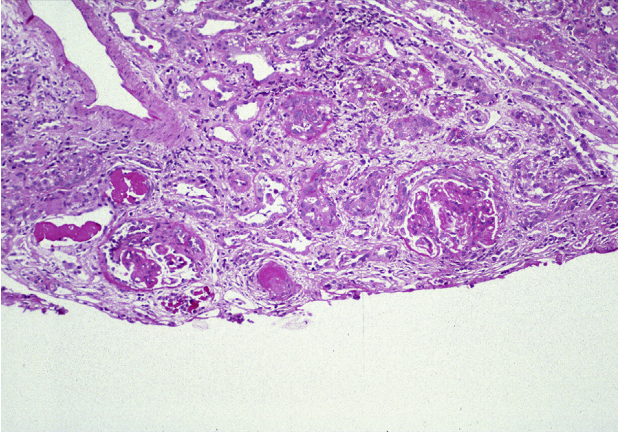

狼疮型肾炎Ⅳ型(弥漫性LN),弥漫性(超过50%)肾小球累及,伴活动性病变。大多数肾小球有轻度系膜区扩张和轻度节段性毛细血管内细胞增生。一个肾小球有明显的节段性细胞增多和小细胞新月体,鲍曼氏膜破裂和坏死延伸到小动脉(PASM染色)

狼疮型肾炎Ⅳ型(弥漫性LN),慢性伴中度间质纤维化、肾小球硬化和纤维细胞新月体,活动伴节段性毛细血管内细胞增生(PAS染色)。